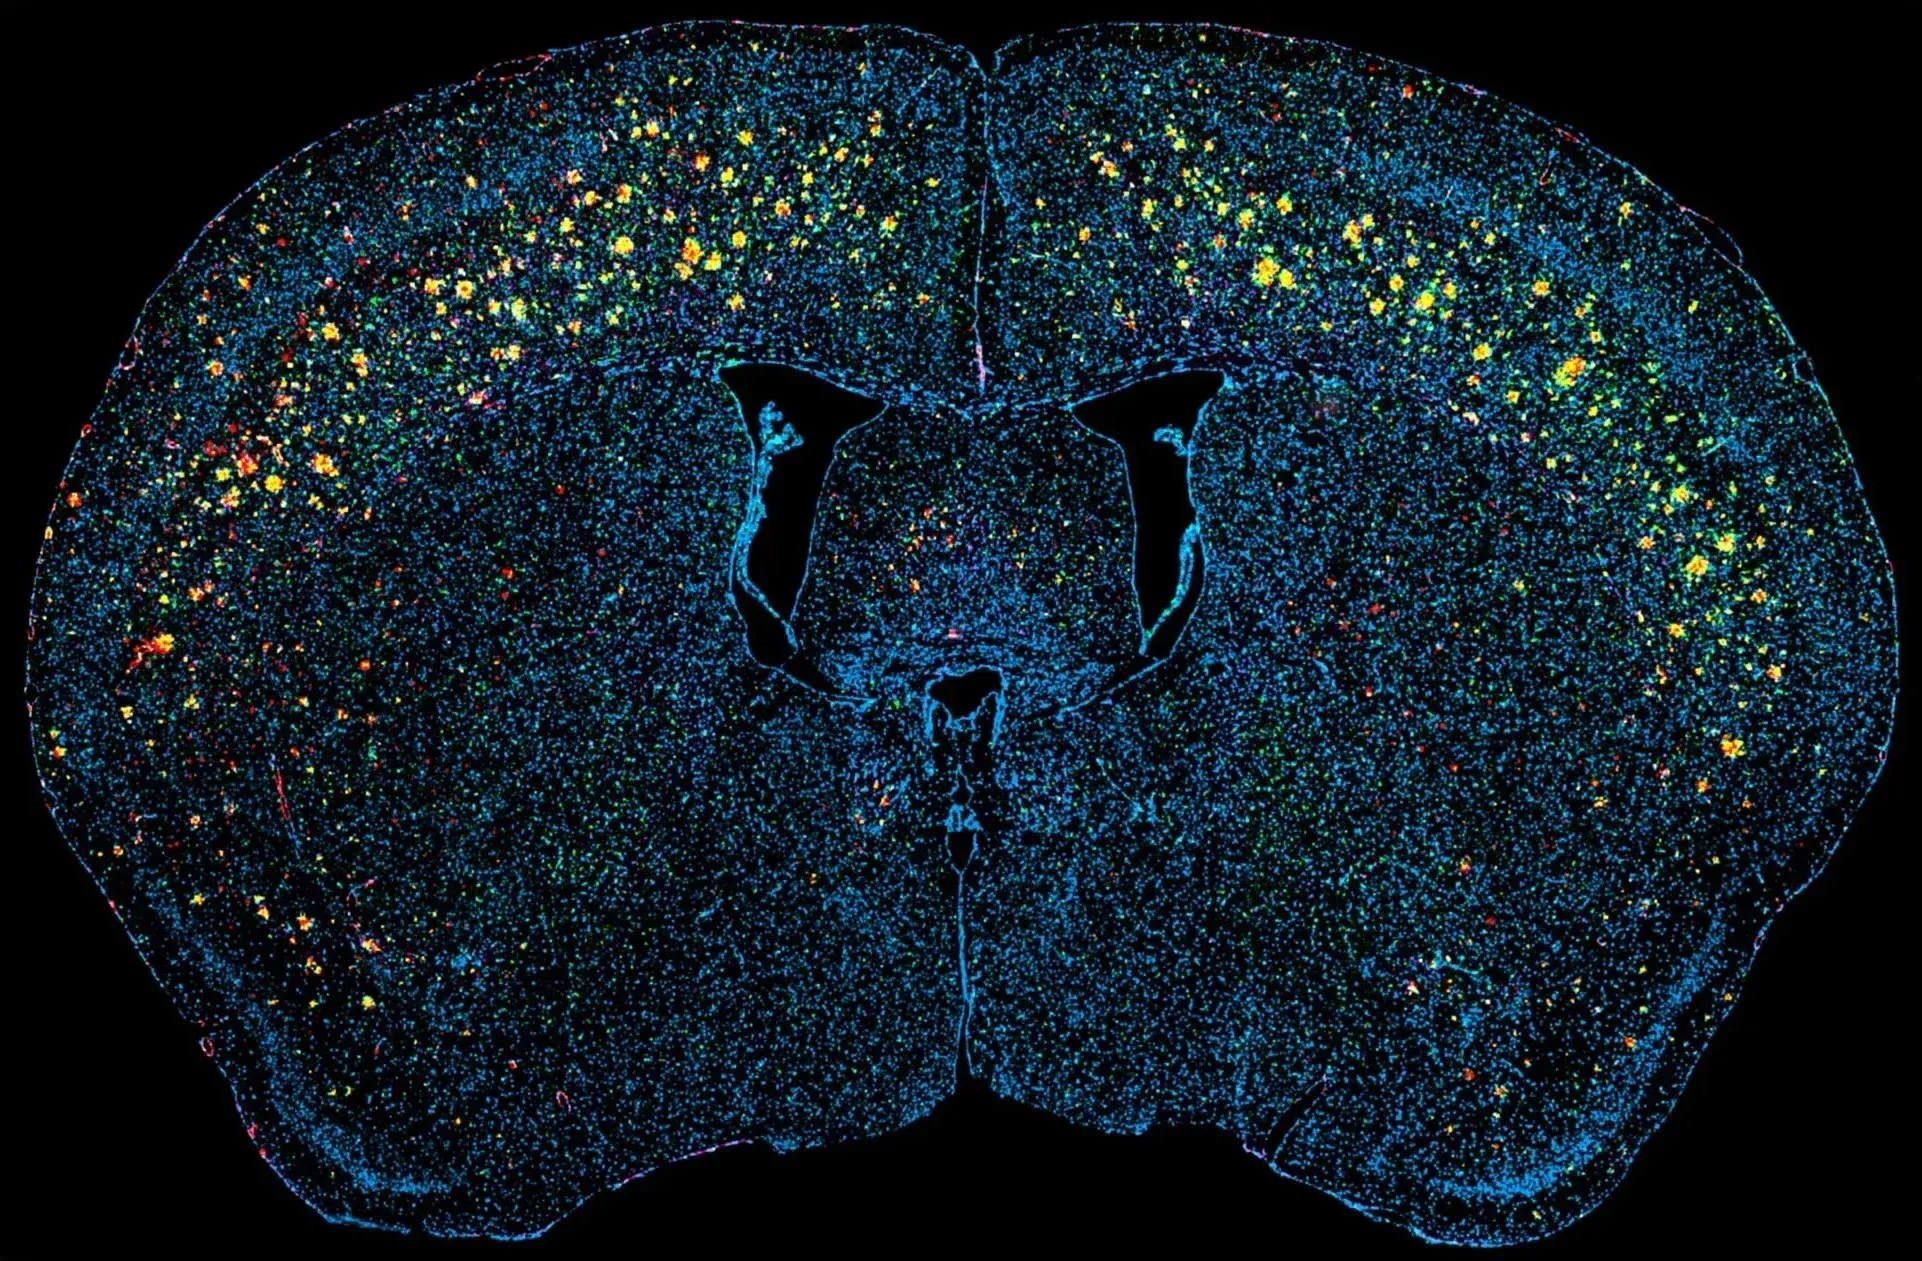

Multiplex immunofluorescence (mIF) image showing Aβ plaques and associated neuroinflammation in our APP/PS1 transgenic mouse model.

The APP/PS1 model that we use for preclinical evaluation of the efficacy of experimental, disease-modifying therapeutic agents is highly reproducible and replicates several key features of human AD. These mice show progressive development amyloid-beta (Aβ) plaques, cerebrovascular pathology, and neuroinflammation. The response to therapeutic intervention can be assessed by several quantitative readouts, including advanced image analysis of multiplex immunofluorescence staining of digitized brain tissue sections.